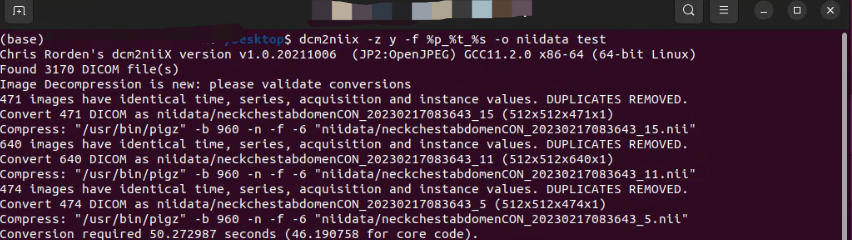

dcm2niix 命令行版

dcm2niix 命令行详细使用说明

dcm2niix 命令中唯一必填的参数是:需要转换的 DICOM 文件夹的位置,该参数始终作为最后一个参数进行提供。例如,dcm2niix ~/dicomdir 将会转换文件夹 “dicomdir” 中的所有 DICOM 文件。但是,你可以指定一些可选参数来影响转换结果。

因此,一个典型的转换命令可能是 dcm2niix -o ~/niftidir -f %p_%s -g y ~/dicomdir。

在这个例子中,软件会在 dicomdir 中查找 DICOM 图像并将转换后的 NIfTI 文件保存在 niftidir 中,输出文件将被压缩,并包含协议名称 (%p) 和序列号 (%s) 作为文件名。

参数很多,但常用的转换命令如下(至少满足我的需求)

dcm2niix -z y -f %i_%d_%s -o niftidir dcmdir

表示将 dcmdir 的所有图像转换到 niftidir 并压缩图像,重命名为 %i_%d_%s